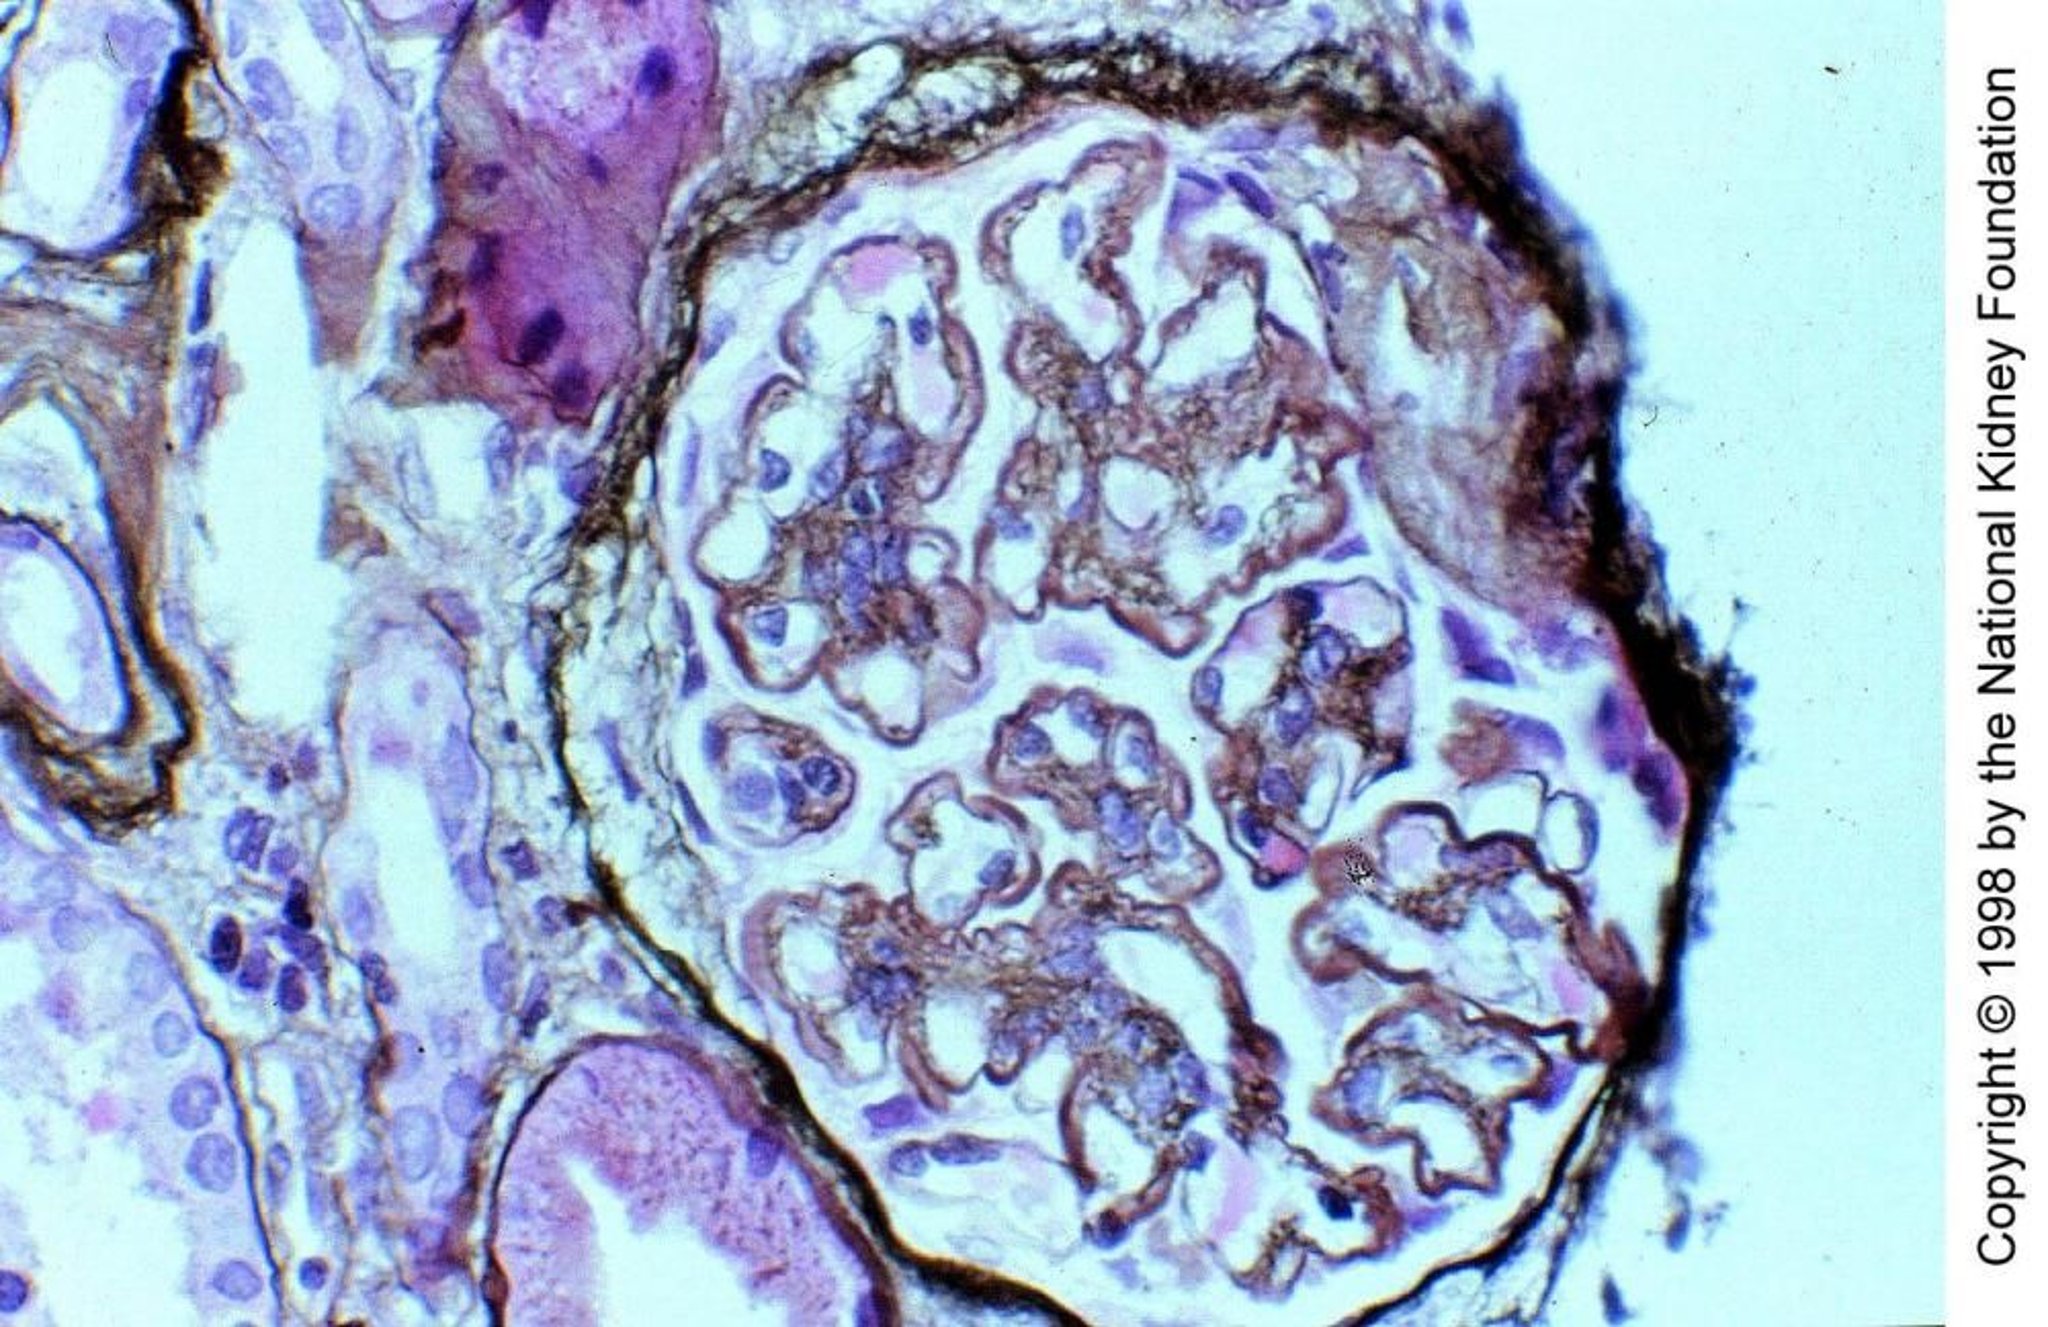

Trong bệnh viêm cầu thận màng tăng sinh qua trung gian bổ thể (MPGN) loại II, yếu tố thận C3, một tự kháng thể IgG có chức năng giống như properdin bằng cách trực tiếp phân cắt C3 thành C3b, kích hoạt bổ thể thông qua con đường thay thế bên trong thành mao mạch cầu thận và gian mạch. Lắng đọng một phần C3 thay thế một phần màng đáy lớp sáng, tạo cho nó một hình dạng dải băng dày và đặc biệt (nhuộm bạc Jones, ×400).

Hình ảnh do bác sĩ Agnes Fogo và American Journal of Kidney Diseases' Atlas of Renal Pathology cung cấp (xem www.ajkd.org).